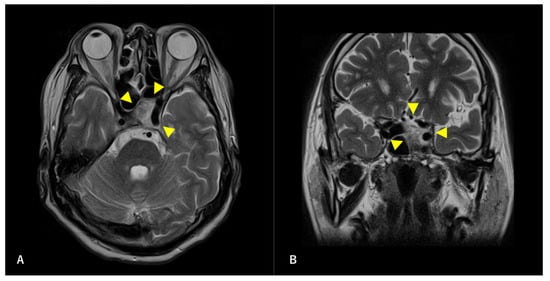

Figure 2. Preoperative T2-weighted magnetic resonance image (MRI) findings. Axial section (A) and coronal (B) images are shown. A high-intensity mass is observed in the left sphenoid sinus. The ICA is surrounded by a mass. Arrowheads indicate tumors.

A 60-year-old man without any symptoms presented to the otorhinolaryngology department with a suspected neoplastic lesion in the left sphenoid sinus, detected on magnetic resonance imaging performed during a physical examination. Imaging modalities showed that the tumor extended from the left sphenoid sinus to the area surrounding the ICA, with associated bone destruction, raising a suspicion of malignancy (Figure 1 and Figure 2). Neither regional lymph node nor distant metastases were observed. An otorhinolaryngologist performed a transnasal biopsy of the tumor under general anesthesia to determine the course of treatment. Immunohistochemical staining was positive for cluster of differentiation (CD) 56, synaptophysin, and chromogranin A. In contrast, cytokeratin AE1/AE3 staining was negative (Figure 3). Notably, there were few S-100 protein-positive cells, which are suggestive of the sustentacular cells typical of ONB. Because the diagnosis was difficult, the pathologists referred the specimens to a more specialized laboratory for additional testing. Further immunohistochemical tests were negative for both Nirenberg and Kim homeobox (NKX) 2.2 and CD99; therefore, the patient was diagnosed with olfactory neuroblastoma with Hymas pathological grade I and Kadish stage C.